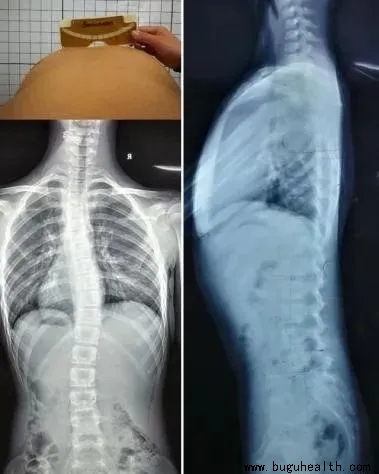

如上图:左边的图是我们正常的脊柱,从后面看应该是一条直线,并且躯干两侧对称。右边的图就是脊柱侧弯,它不仅仅是我们观察到的脊柱向一侧偏移,脊柱侧弯其实是一种脊柱的三维畸形,包括冠状位、矢状位和轴位上的序列异常,分别是:

侧弯

旋转 平背